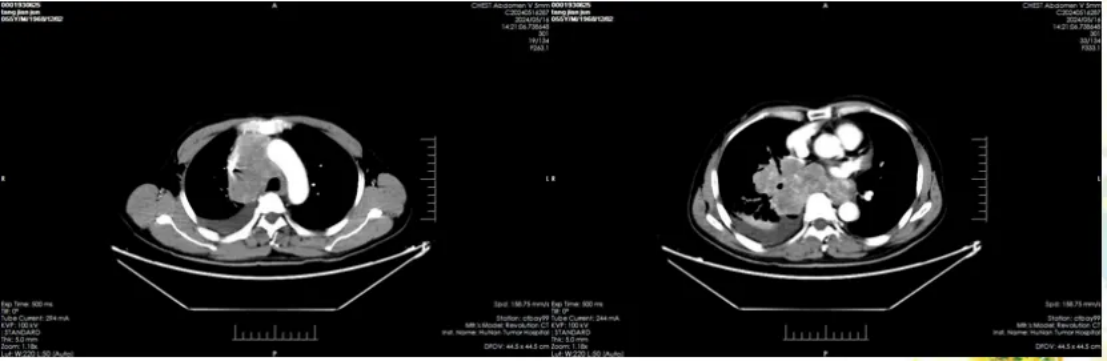

70 岁男性转移性平滑肌肉瘤患者经九线治疗实现四年长期控制,关键是泛癌种测序发现 HRR 基因缺陷,用奥拉帕利联合替莫唑胺,该方案此前仅在子宫平滑肌肉瘤证实有效,为非子宫类型提供参考。